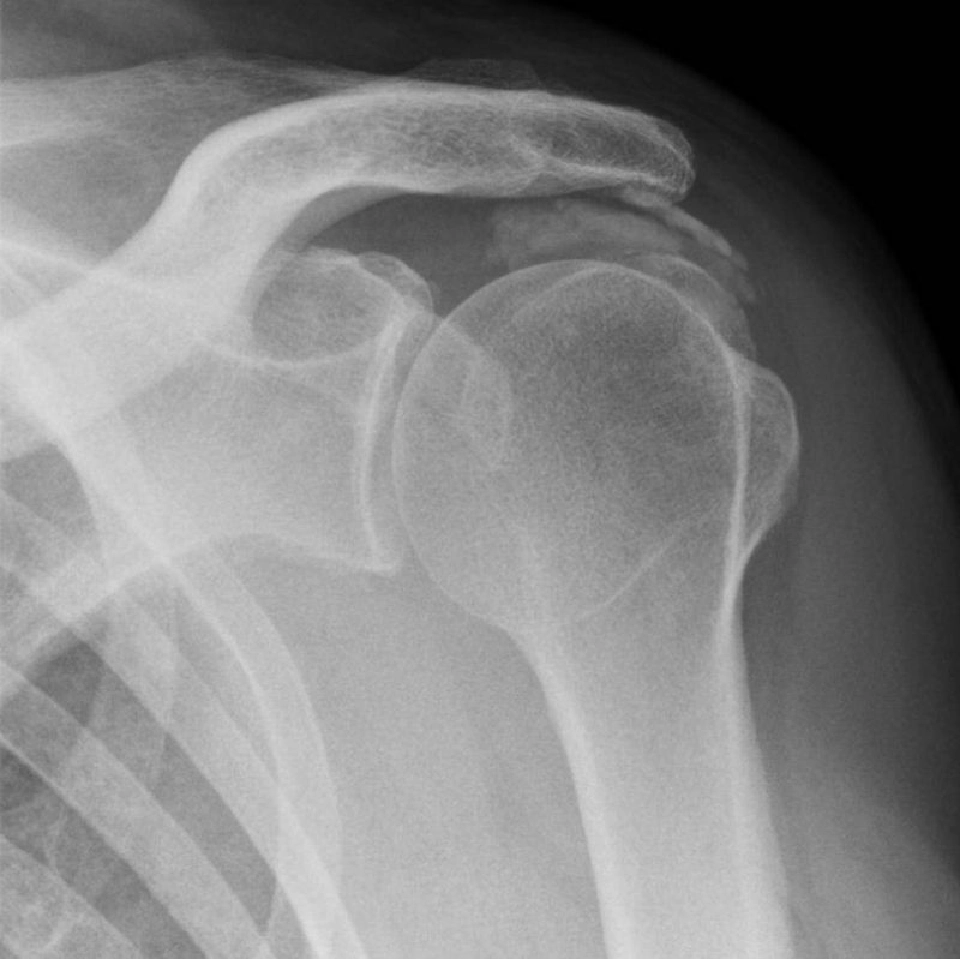

การรักษาเริ่มแรก แพทย์จะทำการวินิจฉัยโรคจากอาการ การซักประวัติและตรวจร่างกาย ร่วมกับการตรวจแบบอื่นเพื่อยืนยันการวินิจฉัย เช่น ตรวจเอกซเรย์เพื่อดูความผิดปกติของกระดูก หรือตรวจ MRI เพื่อวินิจฉัยภาวะเสื่อมหรือการขาดของเส้นเอ็นบริเวณไหล่ และยังสามารถให้รายละเอียดของกระดูกอ่อนและเนื้อเยื่อรอบข้อไหล่ได้ดี โดยแบ่งการรักษาออกเป็น 2 รูปแบบใหญ่ๆ คือ 1.ไม่ต้องผ่าตัด สำหรับกรณีที่ผู้ป่วยมีกระดูกงอกทับเอ็นข้อไหล่ในระยะเริ่มต้น และไม่มีอาการของข้อไหล่ฉีกขาดร่วมด้วย โดยจะใช้วิธีทานยา ฉีดยา หรือทำกายภาพบำบัด ร่วมกับลดกิจกรรมที่กระทำต่อข้อไหล่ ออกกำลังกายเพื่อป้องกันภาวะกล้ามเนื้อฝ่อตัวจากการไม่ได้ใช้งาน บางรายใช้เวลาในการรักษาไม่นาน บางรายรักษาไม่หายทนทรมานต่อความเจ็บปวด หากทำทุกวิธีแล้วยังไม่ดีขึ้นอาจต้องเข้ารับการผ่าตัด